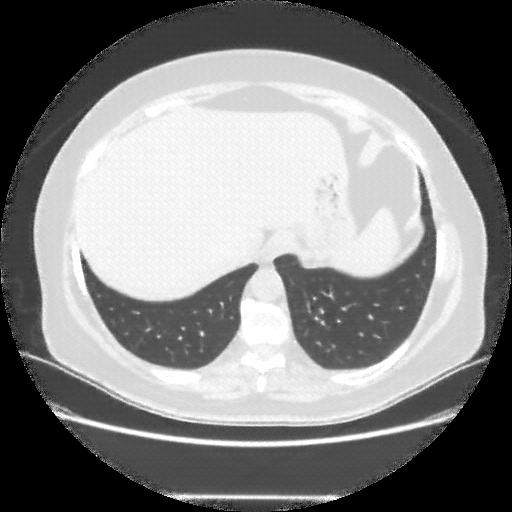

Reconstructed NATIVE CT scan (cycle consistency)

Full window (WL 1023.5, WW 4095 β†’ Low βˆ’1024, High +3071)

Lung window (WL -600, WW 1500 β†’ Low βˆ’1350, High +150)

Mediastinum window (WL 40, WW 400 β†’ Low βˆ’160, High +240)